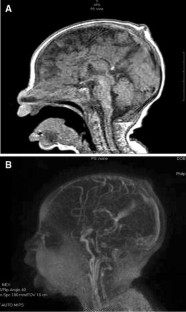

Fig. 1